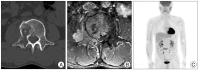

Rapid progression of solitary plasmacytoma to multiple myeloma in lumbar vertebra

The prognosis of solitary plasmacytoma varies greatly, with some patients recovering after surgical removal or local fractional radiation therapy, and others progressing to multiple myeloma years later. Primary detection of progression to multiple myeloma is important in the treatment of solitary plasmacytoma. There have been several analyses of the risk factors involved in the early progression to multiple myeloma. We describe one case of solitary plasmacytoma of the lumbar vertebra that was treated with surgical decompression with stabilization and additional radiotherapy. The patient had no factors associated with rapid progression to multiple myeloma such as age, size, immunologic results, pathological findings, and serum free light chain ratio at the time of diagnosis. However, his condition progressed to multiple myeloma less than two months after the initial diagnosis of solitary plasmacytoma. We suggest that surgeons should be vigilant in watching for rapid progression to multiple myeloma even in case that the patient with solitary plasmacytoma has no risk factors for rapid progression to multiple myeloma.